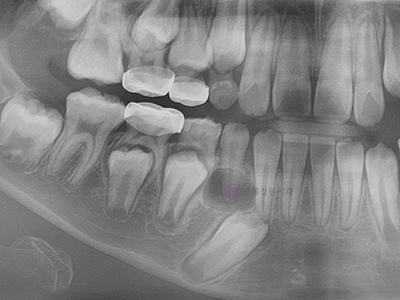

- 매복치 또는 과잉치

만 6~7세부터 유치가 빠지고 영구치가 나기 시작하는데요. 만약에 영구치가 올라오는 맹출 경로에 이상이 생긴다면, 치아가 올라오지 못하고 갇혀 매복치가 되거나, 정상 치아 개수보다 많은 과잉치로 인해 올라오지 못하거나, 교합에 문제가 발생할 수 있습니다. 자신도 모르는 사이 뼈 속에 묻혀있는 치아가 어긋날 수 있는 것입니다.

이런 경우에는 수술적 치료와 동반하여 과잉치를 제거하거나 매복된 치아를 교정적 힘을 이용해 제자리로 위치시키는 치료가 필요합니다.